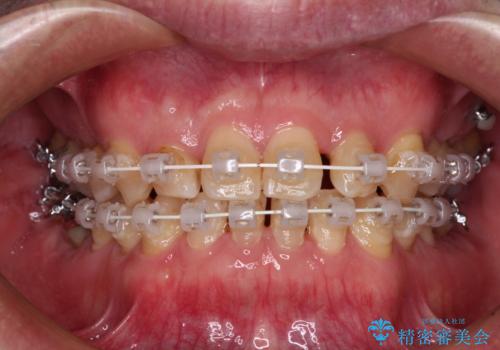

受け口を治す ワイヤー装置での矯正治療

- 上下前歯の反対咬合と左下奥歯の痛みを気にして来院された患者様です。

歯並びや口元の印象、奥歯の咬み合わせから、非抜歯にて矯正治療を行うこととしました。

矯正治療は、ワイヤー装置とマウスピース矯正との選択肢がありましたが、マウスピース矯正は自己管理が煩わしいことを気にされて、目立たないワイヤー装置にて行うこととしました。

インプラント埋入による仮歯の装着や、前歯の反対咬合の改善は比較的スムーズに達成されましたが、舌突出癖などの影響による、歯列全体のスペースを閉じることが難航し、期間がかかってしまいました。